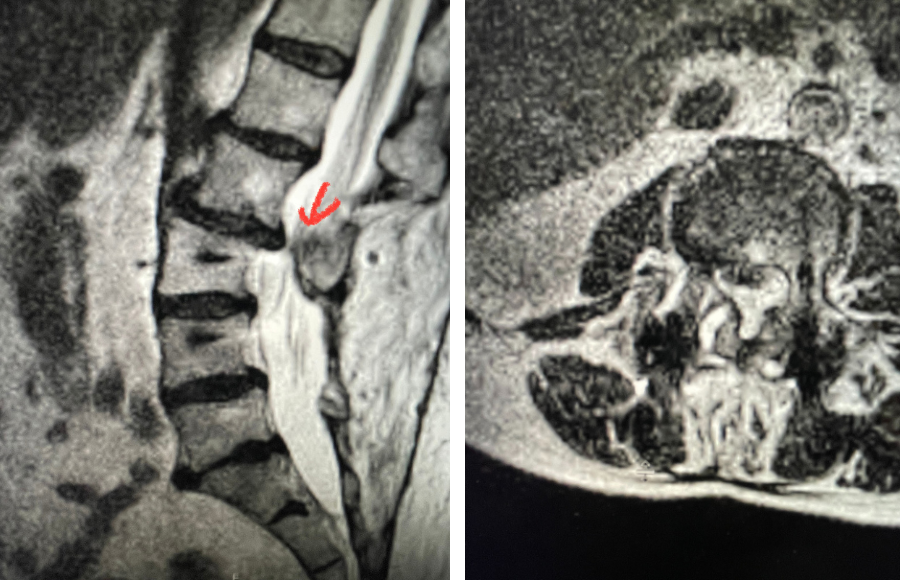

This 42-year-old female presented after complaining of low back pain with intermittent pain going down her left leg and numbness of her feet. She reported having a fall on her back about ten years ago and since then has had back pain. On exam, she had ⅘ weakness of her left dorsiflexion and extensor hallucis longus weakness. MRI revealed a “garden variety” L4-5 grade 1 spondylolisthesis with stenosis, although it was read as having a left pedicle “stress reaction” and suspicion of bilateral spondylotic defects. This was an interesting reading of the MRI, as it is uncommon to have spondylotic defects at L4 which occurs 5-15% versus at L5 which occurs in 85-95% of cases. Most people have an L5-S1 spondylolisthesis with an L5 pars defect. There was thickened ligamentum flavum worse on the left adjacent to the facet with concentric stenosis and bilateral foraminal stenosis. She had tried physical therapy and epidural injections, which did not help. She had trouble standing for long periods of time. Neurologically, she was intact.

Plain lumbar x-rays were done with flexion/extension views. Surprisingly the patient had 4 mm of anterior translation and slight angulation in flexion (Fig 1). This was unexpected because in degenerative spondylolisthesis the patient more commonly has auto stabilized by formation of stabilizing arthritic structures and has no motion on dynamic x-rays. However, approximately 20% of patients will have some degree of translation on flexion-extension x-rays with degenerative L4-5 spondylolisthesis. Because she had failed all means of conservative management, it was felt that the patient would benefit by a lumbar decompression and instrumented fusion because of the acute instability demonstrated on x-rays and her age.